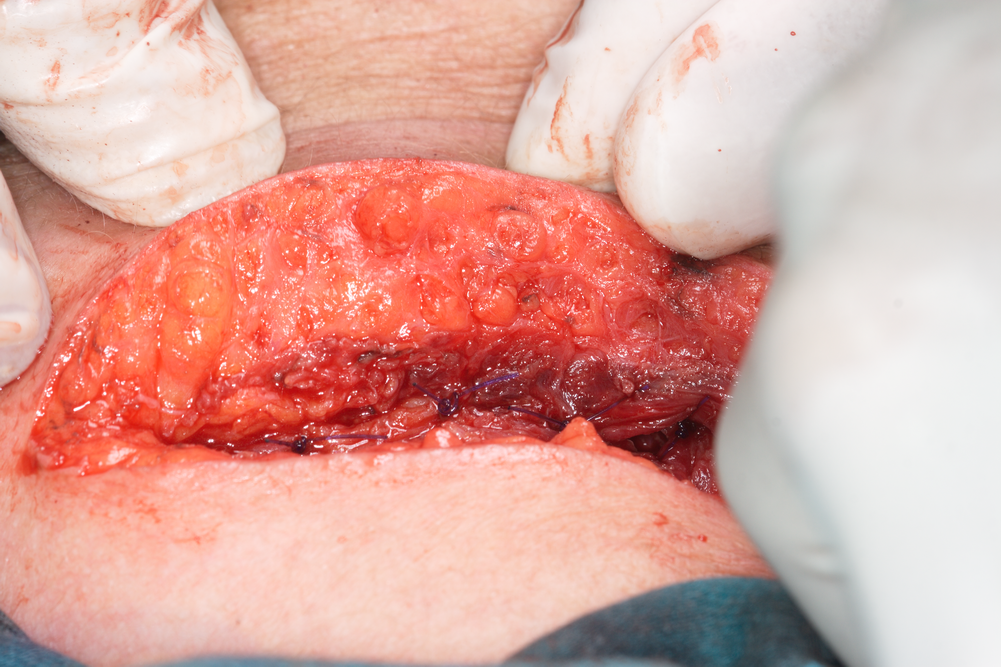

Повърхностен подкожен възпалителен процес, който подлежи на инцизия. Инцизиите на възпалителните процеси също са основни хирургични манипулации и въпреки че спадат към методите за разединяване на тъканите, имат някои свои специфични особености и поради това ще бъдат описани отделно. В лицево - челюстната хирургия се прилагат основно интраорални и екстраорални инцизии - тази класификация е в зависимост от локализацията. Интраоралните са в устната кухина, а екстраоралните - извън нея в областта на кожата на лицето и шията. При много тежки възпалителни процеси е възможна комбинация между двата типа инцизии, при което се осигурява добра възможност за изход на натрупания ексудат.

Технически инцизиите се извършват лесно и това е една от манипулациите, с които всеки специализант по хирургия може да стартира своето обучение и да започне да натрупва клиничен опит. Известна специфика има при по-дълбока локализация на острото възпаление, която за щастие е доста по-рядка. При подкожни или субмукозни процеси е достатъчно дори и само да се пробие кожата (респективно лигавицата) със сонда, при което ексудатът моментално получава изход към външната среда и възпалението стихва. При изпадане на надлежащите тъкани в парабиотични състояния (както е на снимката горе) дори не е необходима местна анестезия - нервните клончета не са в състояние да провеждат импулси и болка на практика няма.

Инцизира се в най-ниската точка на флуктуацията на ексудата, ако има изразена флуктуация. По този начин земната гравитация спомага за постоянната евакуация на натрупаните течности. След това с хемостатичен инструмент се навлиза в дълбочина, инструментът се разтваря и по този начин се осигурява изходен път за изтичане на ексудата. В същото време няма опасност да се среже кръвоносен съд - което би могло да се случи, ако се прониква в дълбочина със скалпел или ножица.

Евакуация на гнойния ексудат